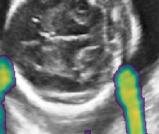

V-C Automated Biometric Measurements

We integrate our shadow confidence maps into an automatic biometric measurement approach [32], and show the biometric measurement performance (measured by DICE) before and after adding shadow confidence maps.

Similar to the ultrasound standard plane classification, shadow confidence maps are integrated into a biometric estimation model described in [32] as an extral channel. Specifically, we train and test four fully convolutional networks with the same hyper-parameters as detailed in [32], and use the same ellipse fitting algorithm described therein. The first network is trained only on the image data used in [32]. The other three networks are trained with an additional input channel for shadow confidence maps that are separately generated by the baseline, the proposed, and the proposedAG method.

We show three examples that are affected by shadows, and show their biometric measurement results in Table V. From this experiment, we find that biometric measurement performance is boosted by up to for problematic failure cases after adding shadow confidence maps. The average performance on the entire test data set stays almost the same since only a small proportion of the test images are affected by strong shadows, mainly because of the image acquisition by highly skilled sonographers.

-H Examples for Biometric Measurement

We visualize the biometric measurement of the three examples shown in Table V. Fig. 16 demonstrates that, for the cases affected by shadow artifacts, the segmentation performance (“EI_seg DICE”) is improved after adding shadow confidence maps as an extra channel. From the first row to the third row in Fig. 16, these three samples are respectively #1, #2 and #3 samples in Table V.